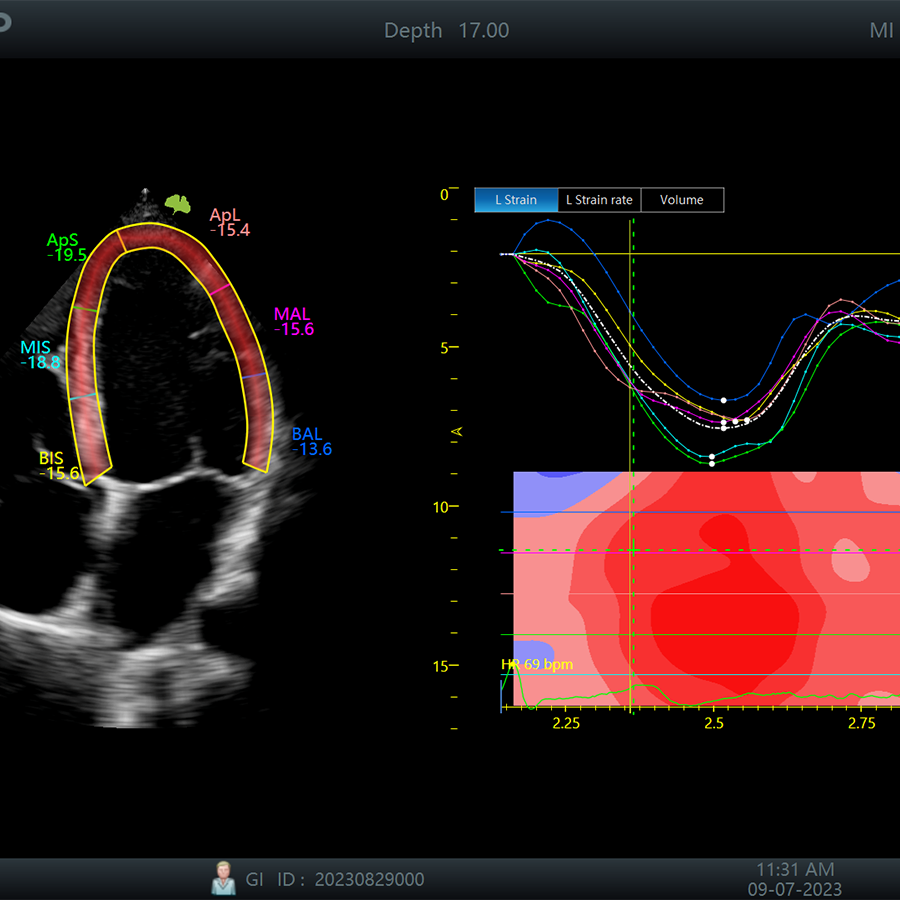

Cardiología

- CW

- ECG

- TVI

- TD

- Eco-Estrés

- Strain

- Strain (VD,AI)

- EF Automática

- Multi-Doppler

- AMAS

- PWV

- M Doppler Color

- M Doppler Tisular

- MAM